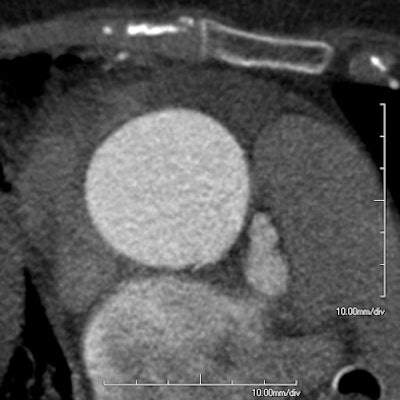

| At ECG-gated cornary CTA, a small defect can be seen in the aortic wall of a 74-year-old woman referred for suspected pulmonary embolism. The lesion was found to correspond to a 12-mm supercoronary tear in the aortic wall at surgery. Image courtesy of Dr. Sebastian Schotten. |

"Intraoperatively, four patients were found to have limited intimal tears in the ascending aorta, and of these, in only two patients was the dissection revealed by CT," Schotten said. "These may range from very limited tears in the aortic wall to deeper and more extended tears with subsequent bleeding in the adventitia, but without classic dissection."

ECG gating does limit motion artifacts of the aortic root and ascending aorta, and as a result it improves the identification of small intimal injuries, Schotten said. However, even with ECG gating not all subtle aortic dissections could be identified in the study.